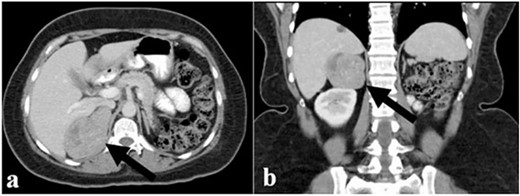

The endocrinological study showed a hypersecretion of cortisol with suppressed ACTH (550 mcg/l, ACTH 1.1 ng/ml, urinary free cortisol 255 mcg/24 h, positive overnight Nugent test). The serum concentration of renin and aldosterone and the urinary concentration of metanephrine are instead normal. Therefore, the patient underwent an abdominal CT scan that showed a right adrenal lesion of about 7 cm with an adenomatous appearance (Fig. 1). The saggital 3D reconstruction of CT scan in venous phase had raised the suspicion of short course of the adrenal vein in the lower lateral lip of the mass (Fig. 2). To better define the relationship between the neoplasm and the inferior vena cava, the vascularization of the adrenal gland with any anatomical anomalies and the specific location of the middle adrenal vein, a 3D printed model was created in 1:1 size based on the preoperative CT scan.

(a) and (b) The abdominal CT scan showed a large right adrenal tumor.